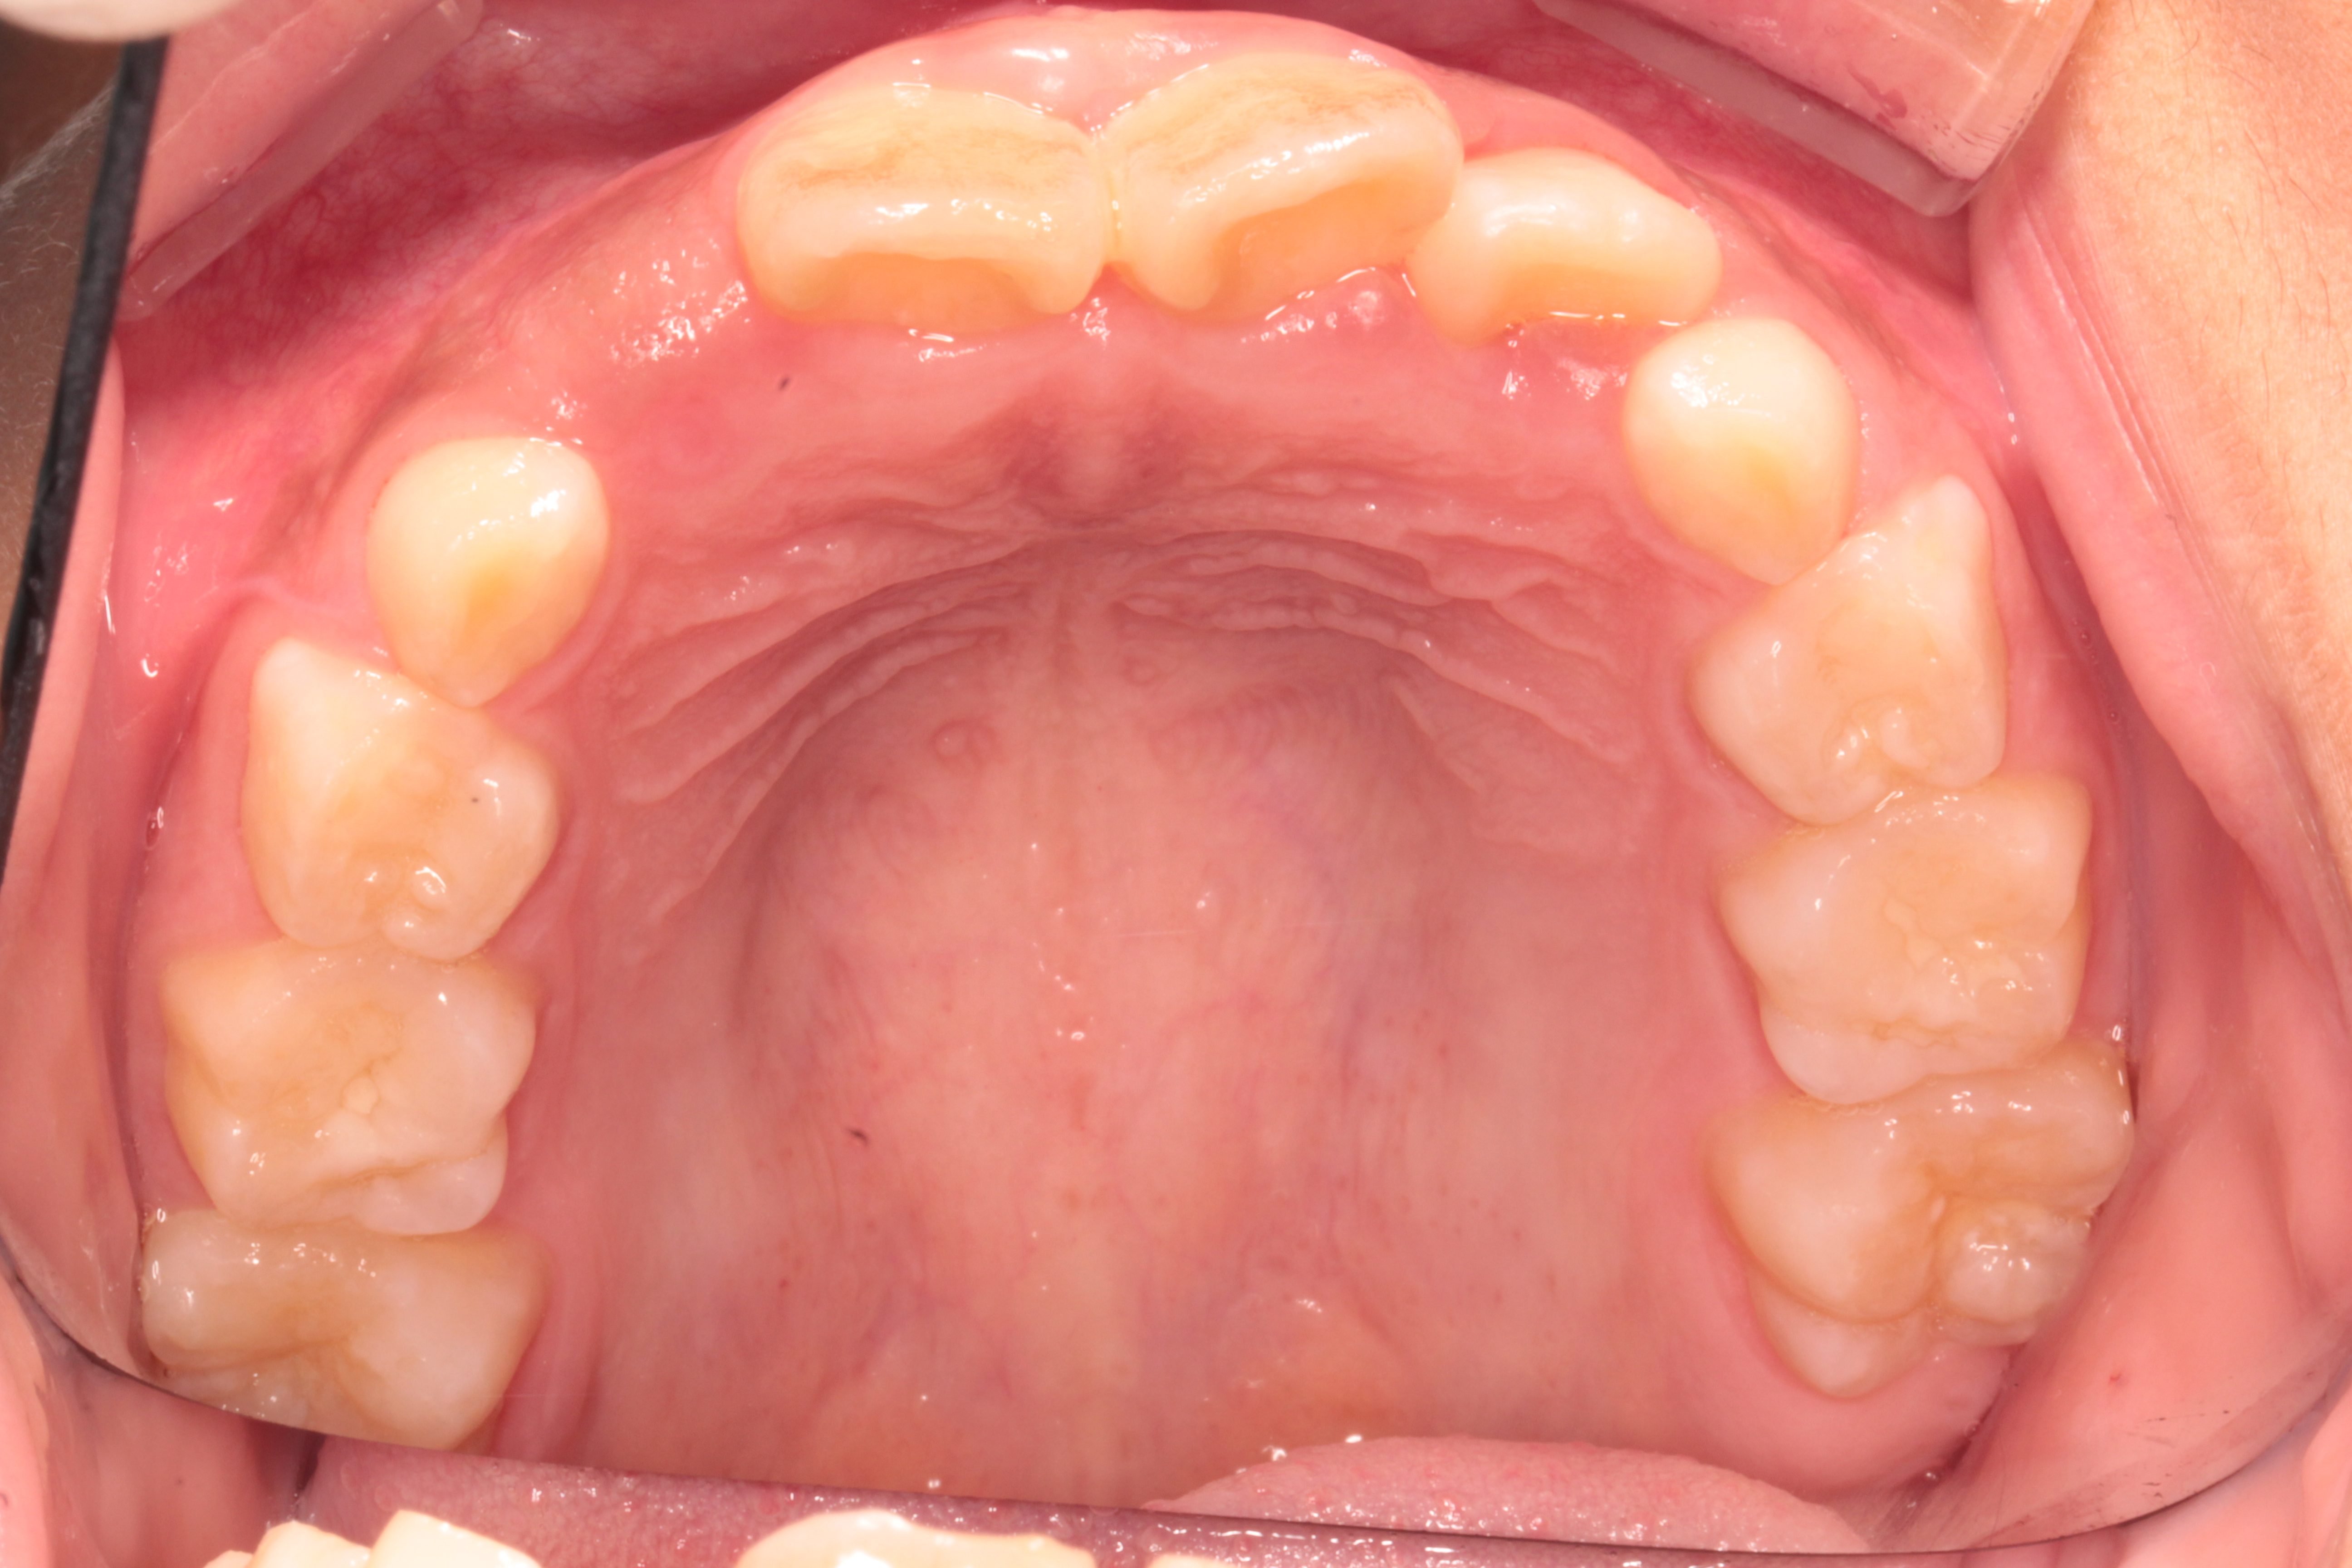

乳歯からの子供(小学生 長男)の歯並び育成

小学校3年生男子で歯並びを主訴としてご来院されました。

被せ物を歯に装着して高さをを作り上下的・垂直的な成長を促し、ワイヤーを装着することで水平的に歯並びの成長を促していきました。

約2.5年の治療後です。

歯を抜くことなく、自然な歯並びにすることができました。